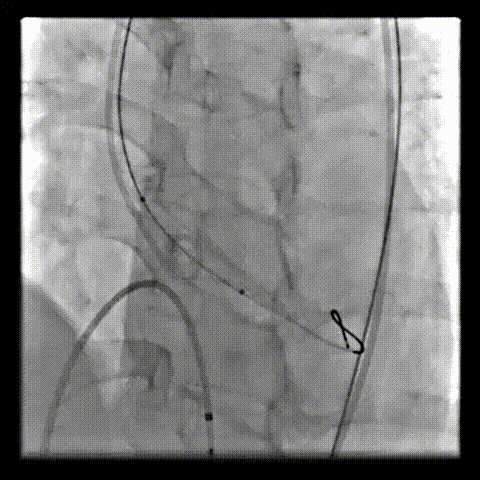

术中影像

根部造影可见返流;20mm球囊预扩,LCA灌注缝隙狭小

预置LCA保护;第一次释放,

团状钙化挤压导致瓣膜(AV23)少量下滑

回收后重新定位,第二次释放,

瓣膜(AV23)深度仍未达到最佳预期

完全回收,第三次定位释放,瓣膜(AV23)位置良好